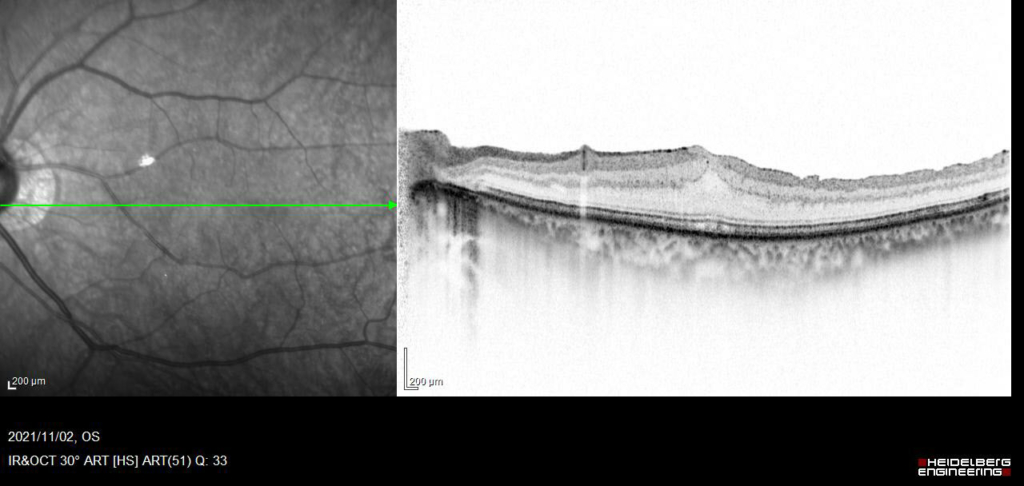

黄斑耳側の網膜表面に膜組織による高反射がみられ、血管が蛇行し偏位がみられる。

ERMを示す高反射が網膜前面にみられ、皺壁を形成している。黄斑網膜は肥厚し、中心窩は外顆粒層の挙上により三角形に隆起している。